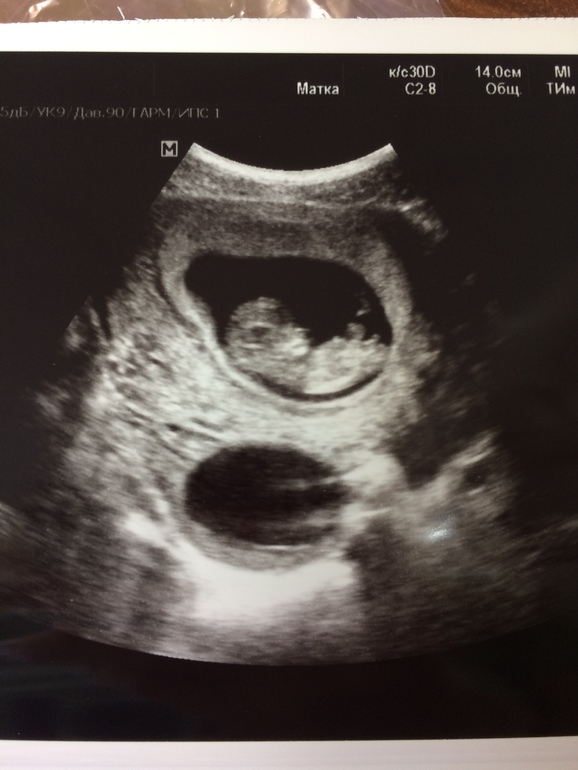

Марина Тужилкина

А здесь девочка) судя логике мужа автора.

Ну су по его логике- мальчик.